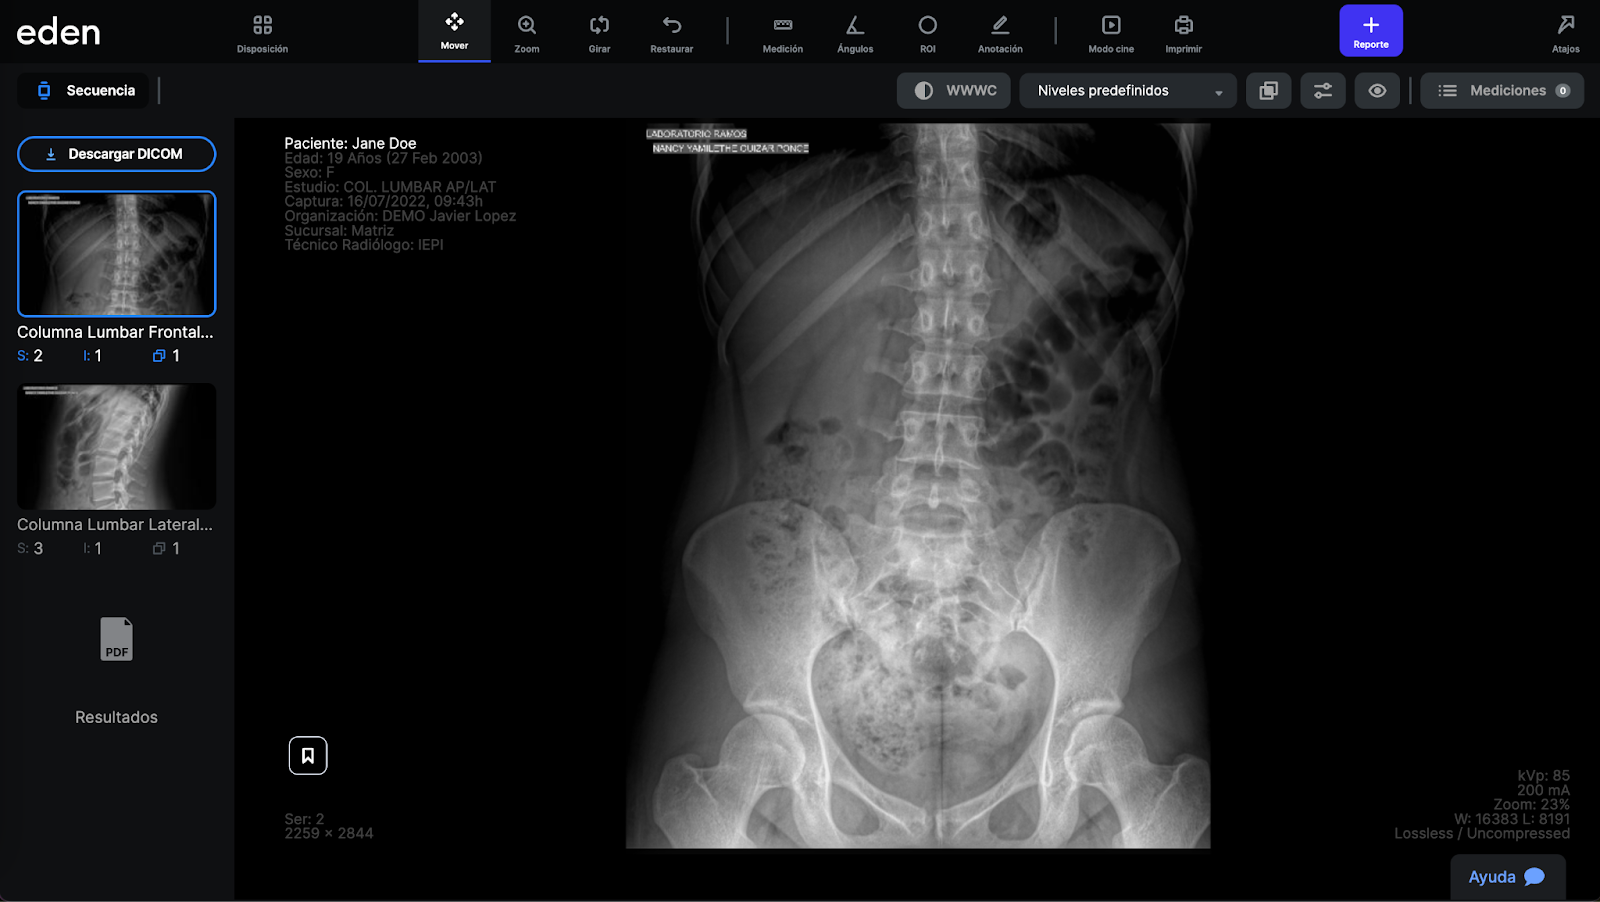

Para acceder al estudio, damos clic sobre el nombre del paciente. Se abrirá una nueva pestaña con la pantalla principal del visor DICOM:

La pantalla se divide en varias secciones:

La descripción de cada sección sigue a continuación:

Panel de imágenes y archivos del estudio (Secuencia):

Información del estudio DICOM:

Estos bloques de información se muestran en la esquina superior izquierda, así como en las dos esquinas inferiores del estudio. Muestran información demográfica, información del estudio, fecha de captura, organización o institución, sucursal, así como información de la serie de imágenes, información de la resolución, información de cortes, información de compresión, así como información inherente a cada equipo de imagen como puede ser el voltaje de los RX con los que se tomó la imagen. Esta información depende de que haya sido capturada correctamente en la modalidad y/o en el sistema Eden.